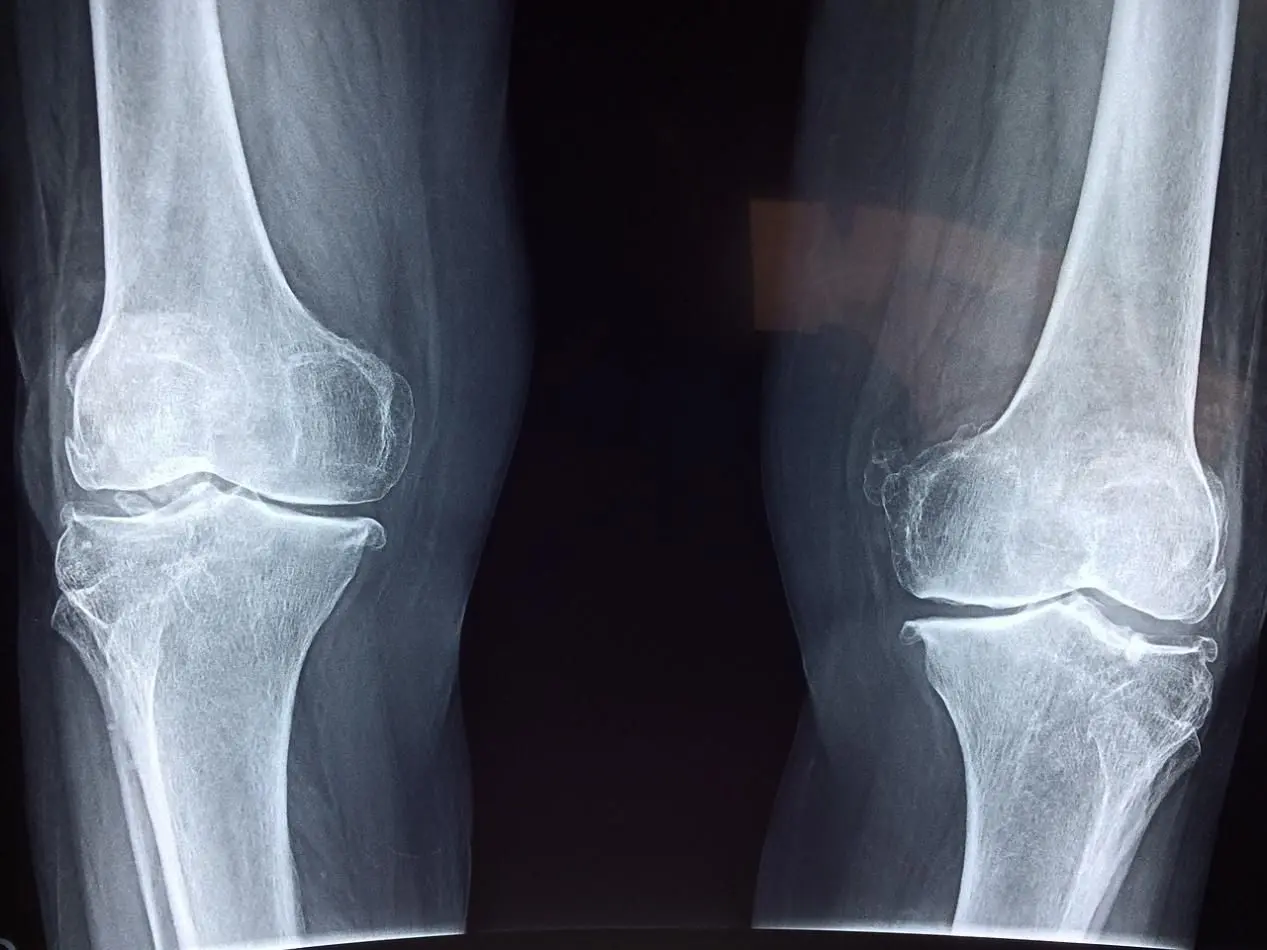

Our Orthopedic Department is a specialized unit dedicated to the prevention, diagnosis, and treatment of musculoskeletal disorders. The department is staffed with skilled orthopedic physicians who possess extensive clinical experience. They excel in addressing various musculoskeletal issues, including knee joint injuries, arthritis, hip joint injuries, and more. Additionally, our department is equipped with state-of-the-art medical facilities, including advanced X-ray, CT scanning, and MRI equipment, enabling comprehensive assessments of patients' musculoskeletal conditions.

The Orthopedic Department focuses primarily on diagnosing and treating joint injuries, with key clinical tasks and research directions including rehabilitation studies related to knee joints, hip joints, shoulder joints, wrist joints, osteoporosis, and more. The department has undertaken extensive rehabilitation and research efforts, holding a leading position nationally in this field.